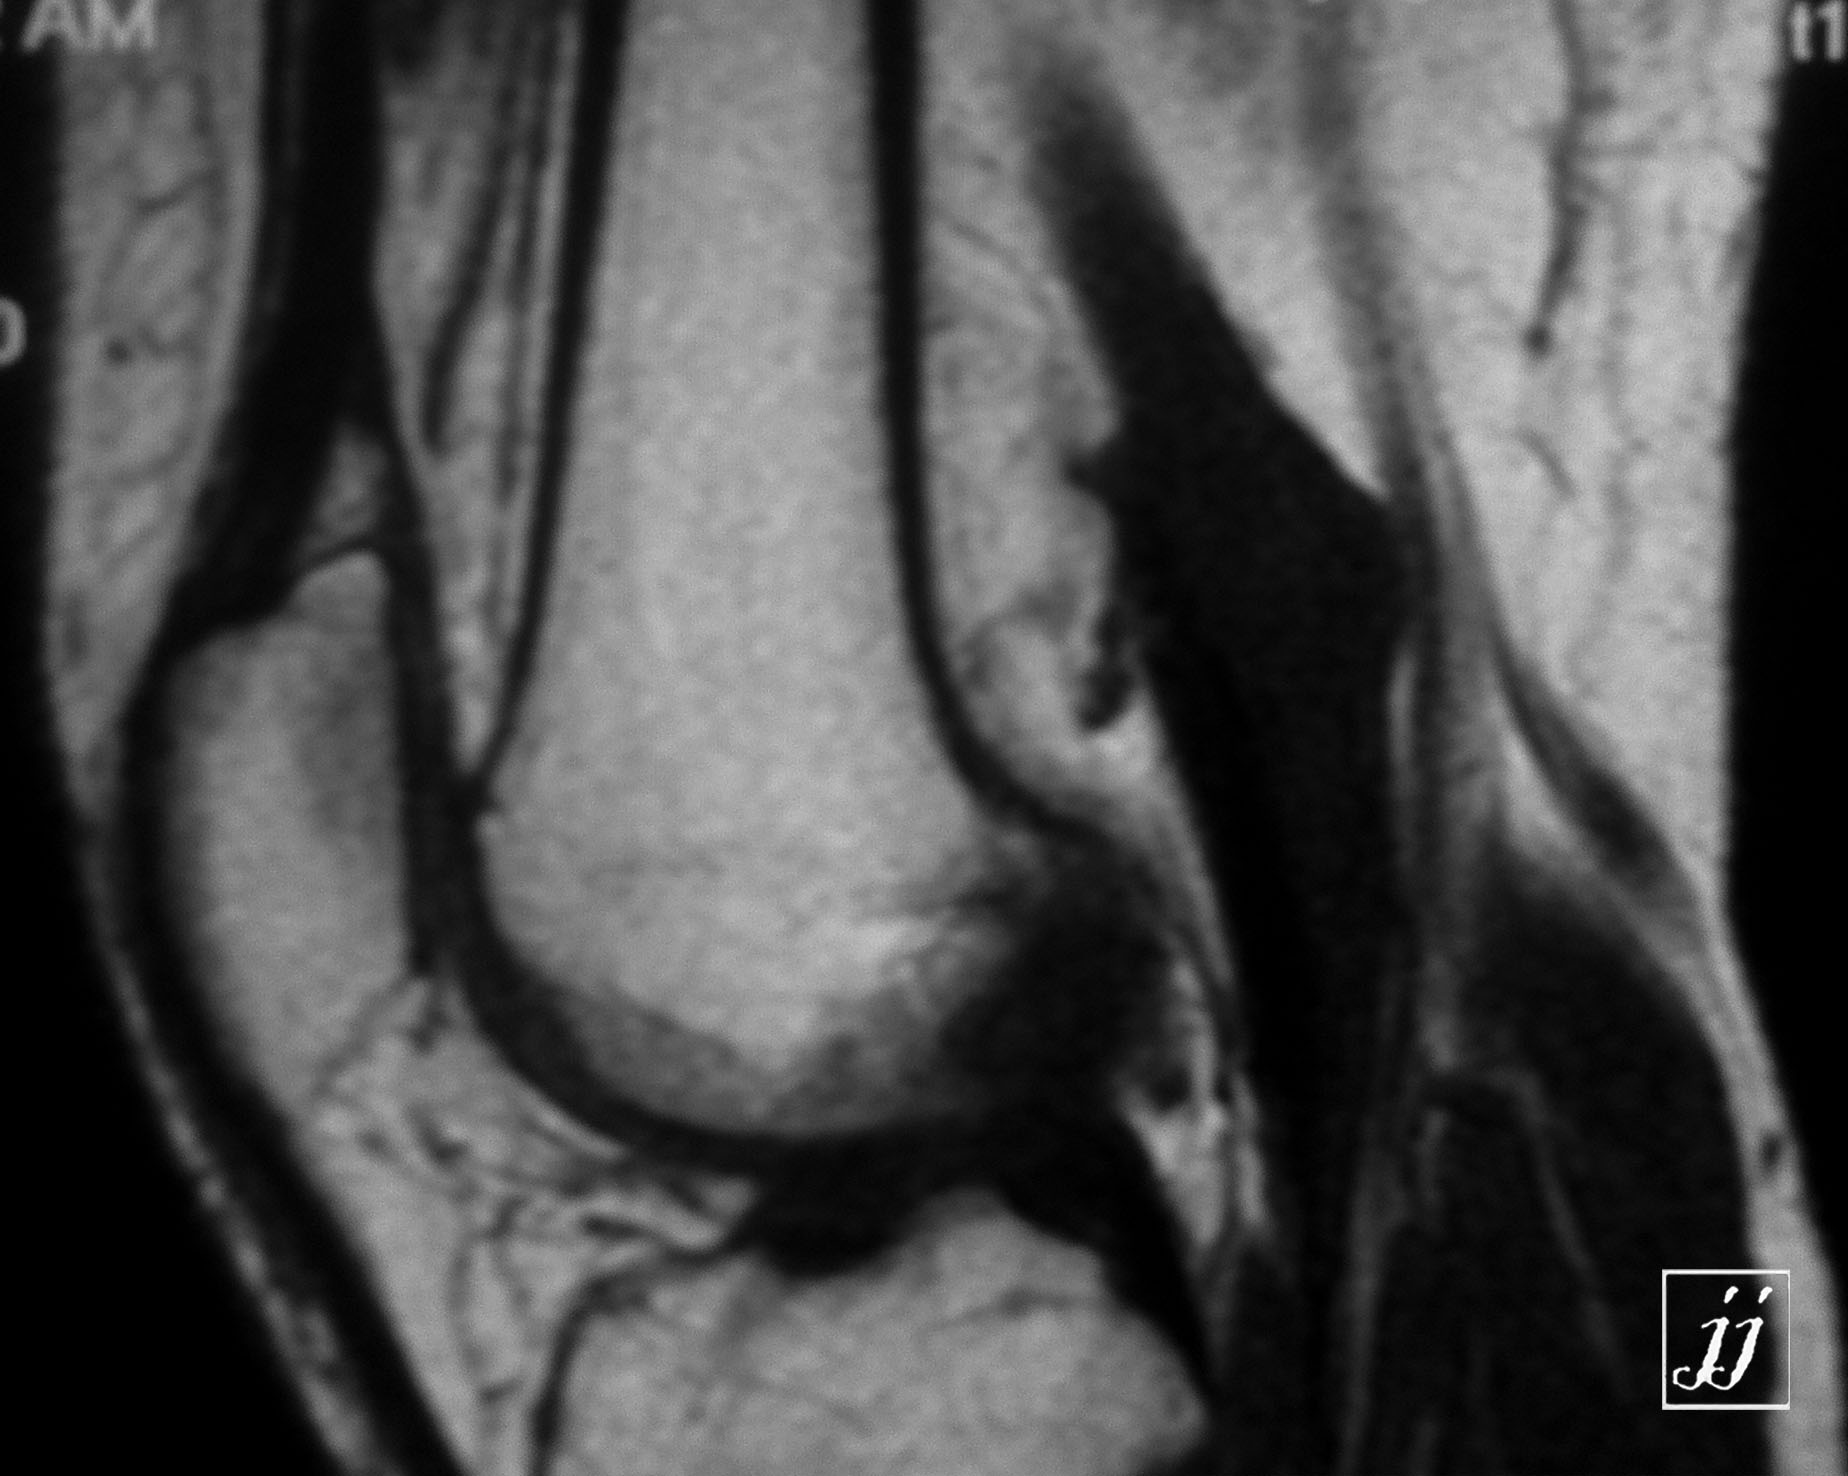

MSK- bi lateral popliteal cyst (5)